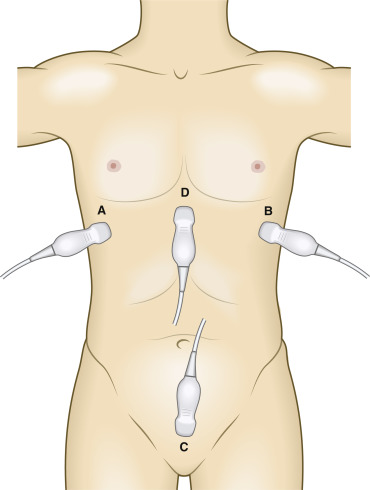

Location and Relevant Normal Anatomy

The FAST exam evaluates the abdomen for internal bleeding. Therefore, anatomic locations for probe placement include the A) right flank at Morrison’s pouch, B) the left flank at the splenorenal process, C) the suprapubic location above the bladder and D) the subxiphoid cardiac window .